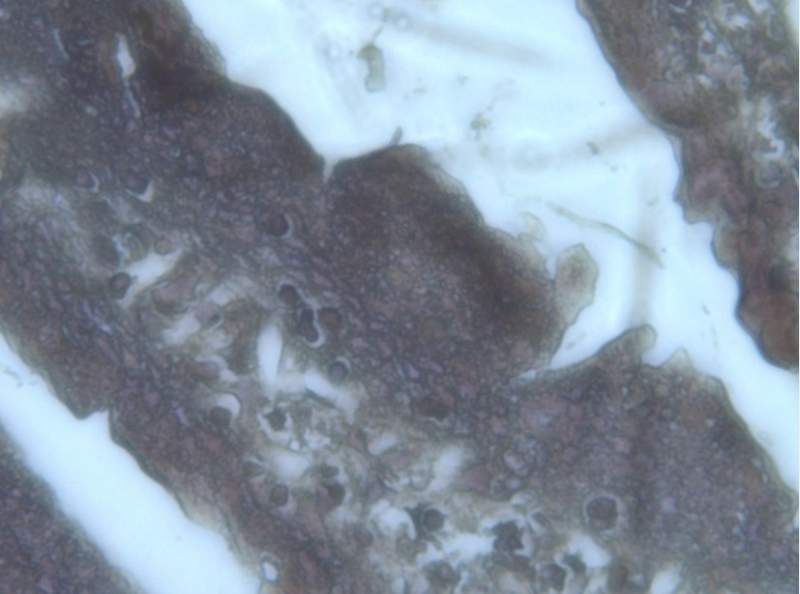

¿»ùʯÀ¯ÇÐÆ¬×¨ÓÃtunelÊÔ¼ÁºÐ×ö³öÀ´µÄСÊóµòÍö£¬½á¹ûÌØ±ð¹ÖÒ죬Çë¸ßÊÖ°ïæ·ÖÎö£¡ ÒÑÓÐ1È˲ÎÓë